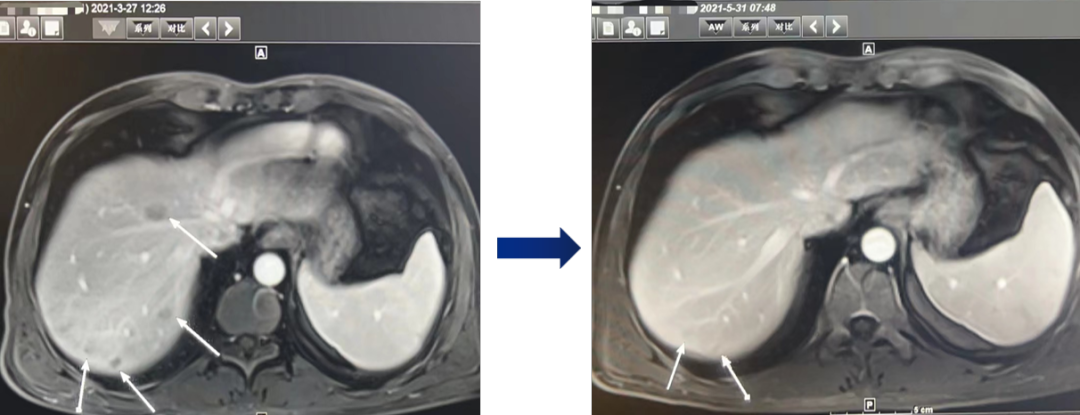

在全球,结直肠癌是发病率位居第三位、病死率位居第二位的肿瘤。肠镜筛查的普及以及手术方式的提升显著降低了结直肠癌的死亡率,但仍有一部分患者在初诊时已发展为晚期,失去手术根治的机会,且预后较差,5年生存率仅12%。许多转移性结直肠癌(mCRC)患者在经历一线治疗后,面临无药可用的困境。近年来,随着靶免联合治疗在系统治疗中逐渐前移,各种靶向治疗药物在mCRC的诊疗中也越发举足轻重。本文分享2例晚期结肠癌患者的诊疗经过,呈现瑞戈非尼在二线治疗为患者带来长生存的治疗价值及其良好的后线应用前景,以期为临床医生提供诊疗借鉴。 病例提供:海军军医大学附属长征医院 王湛 王湛 病例基本情况 一般信息:女 ,58岁。2020年10月,患者无明显诱因出现腹胀,无伴随症状,未予重视。后腹胀进行性加重,2020年11月中旬下腹部隐痛,与进食及体位变化无关,无肩背部放射痛。 辅助检查: 腹部超声:腹腔积液。 腹水脱落细胞病理:腺癌。 腹部增强CT:结肠肝曲癌;腹盆腔积液,腹盆腔腹膜多发转移。 结肠镜(2020-12-4):升结肠近肝曲见隆起型新生物,范围约4cm,新生物表面分叶状,质脆,触之易出血。肠腔狭窄,内镜尚可通过。 2020-12-8病理:横结肠,中分化腺癌,含部分粘液腺癌。 一线治疗2020-12-03至2021-02-24 CAPEOX+贝伐珠单抗 治疗4周期 病情进展,腹胀、腹痛加重,腹水增加。 2021-3-31 PET-CT:腹腔内及腹膜、脾脏、纵隔及右侧心膈角区、左侧锁骨区多发代谢增高灶,结合病史,考虑转移;双肺转移;腹腔及盆腔积液;结肠显示欠清,请结合肠镜检查;双侧胸腔少量积液,左肺下叶部分不张;双肺少许慢性炎症;右肝血管瘤;左肾结石。;子宫术后,痔疮可能;脊柱退变,腰3不稳,腰3/4、4/5、腰5/骶1椎间盘突出。 PFS:3个月 2021-4-6,完善基因检测(腹水标本):KRAS/APC/TERT/TP53/ target=_blank class=infotextkey>P53 突变,TMB 7.98/Mb,MSS 二线治疗,2021-04-02至2021-12 2021-3-31 2021-6-2 2021-8-6肠镜:结肠镜顺利插至回盲部,回盲瓣呈唇状。结直肠粘膜呈桔红色,光滑湿润,有光泽。血管纹理呈树枝状,清晰可见。 PFS:8月 三线治疗,2021-12-13至2022-01-23 三氧化二砷 2021-6-2 2021-11-22 2021-11-22 2022-2-8 PFS:2月 四线治疗,2022-02-10 化疗+免疫+瑞戈非尼+三氧化二砷 2022-2-10开始使用小剂量化疗(雷替曲塞+奥沙利铂+伊立替康)+免疫(信迪利单抗)+瑞戈非尼+三氧化二砷治疗。 疗效评估(2022-9-20):患者病情再次取得缓解。 2022-9-22至今采用维持治疗,降低治疗强度:雷替曲塞 +信迪利单抗+瑞戈非尼+三氧化二砷 2022-9-20 2023-2-8 PFS:13个月+ 该患者为中年女性,诊断为晚期多发转移性结肠癌,基因检测提示KRAS突变,BRAF、NRAS野生型,微卫星稳定,无法进行根治性切除。一线治疗加予CAPEOX联合贝伐珠单抗,治疗4周期后出现病情进展,腹胀、腹痛加重,腹腔积液增加,二线采用瑞戈非尼联合免疫和化疗,患者耐受良好,1周期后腹胀明显缓解,全身状态、PET-CT、肠镜结果较之前明显改善,继续原方案治疗,PFS长达8月。二线治疗进展后完善基因检测,发现TP53 突变,经与患者充分沟通,三线治疗采用三氧化二砷,疗效不佳。四线治疗在三氧化二砷基础上加用瑞戈非尼+免疫+化疗,患者病情再次取得缓解,PFS 超过13个月。近年来,随着精准医学及靶向、免疫治疗的发展,mCRC的管理与治疗策略的制定也变得复杂,合理选择治疗手段、优化全程管理至关重要。本例患者经历了一线化疗联合免疫治疗后疾病出现快速进展,我们个体化地在二线治疗中应用瑞戈非尼联合方案,患者疾病得到控制,PFS 8个月。在四线治疗方案中,再次挑战瑞戈非尼,依然获得较好的疾病控制效果,目前PFS已超过13个月。基于CORRECT和CONCUR研究,瑞戈非尼用于mCRC三线治疗已积累大量临床数据,目前已成为mCRC三线标准治疗方案。此外,REGONIVO、REGOTORI以及RIN方案证实了瑞戈非尼联合免疫治疗MSS型肠癌取得更长的总生存期。一线治疗后疾病进展,能否将瑞戈非尼使用前移,在二线治疗中加用以进一步延长患者生存,以及前线已经暴露过瑞戈非尼,后线再次使用瑞戈非尼是否可行,仍待在临床研究中进一步证实。 02 病例分享二 病例提供:海军军医大学第一附属医院 王薇 王薇 病例基本情况 一般信息:男性,41岁。2020年10月8日,无明显诱因下出现便血,为鲜红色,伴肛门坠胀不适,无排便习惯改变,无腹胀,无消瘦。1997年因“胃溃疡”行胃部幽门切除术;2019年行混合痔手术。 辅助检查: CEA 3.4ng/ml,CA199 3.52u/ml。 当地医院肠镜(2020-11-20):(距肛缘8-10cm)可见粘膜不规则隆起,表面溃烂,易出血。 肠镜活检病理:(直肠)中分化腺癌。 盆腔MRI增强(2020-11-26):直肠中段癌,考虑mrT3N1Mx,MRF-,EMVI-。 肝脏MRI增强(2020-11-27):未见明显异常。 治疗经过 首次手术治疗2020-12-09 腹腔镜辅助直肠癌拖出式适形切除术+末端回肠造口术 术中探查:直肠下段肿物,质硬,未浸润浆膜层,周围系膜未见肿大淋巴结。肿瘤大小约4*4*2cm,占肠腔1/2周,系膜完整。 术后病理: 直肠溃疡型肿瘤大小4.5x3.5x1.5cm;中至低分化腺癌,部分为粘膜腺癌;浸润至外膜层; 癌结节( 3枚+)、脉管癌栓(+)、神经侵犯(+)、肿瘤出芽(+,PDC1级);上下切缘(-)、环周切缘(-)、吻合圈(-);周围淋巴结(2/6),直肠外膜淋巴结(2/4),最高群淋巴结(0/4); 基因分型:KRAS Exon-2 G12D突变,NRAS、BRAF、PIK3野生型;免疫组化:MSH2(+),MSH6(+),MLH1 (+),PMS2(+),pMMR;Ki-67 80%。 术后分期:pT3N2aMx IIIB期 术后辅助治疗(XELOX方案) XELOX方案化疗3周期; 拟行盆腔放疗50gy/25次,2021-03-25起放疗6次 术后复查 肝脏MRI增强(2021-03-27):肝脏多发结节,较前为新发,考虑肝内多发转移瘤 一线治疗,2021-04-22至2021-06-24 mXELIRI+贝伐珠单抗 治疗4周期 患者治疗后出现恶心呕吐,胃纳明显减退,Ⅱ°粒细胞下降,腹泻,脱发,轻度手足皮肤反应,手足冰凉,心悸。患者无法耐受继续治疗 维持治疗,2021-7-15至2021-8-26,卡培他滨+贝伐珠单抗,共计治疗3周期 肝脏MRI增强(2021-5-31、2021-8-24):肝右后叶上段7mm小结节灶,转移不除外,腹膜后稍大淋巴结较前相仿,随访。 2021-3-27与2021-5-31的肝脏MRI增强对比图 2021-8-24 肝脏MRI增强 盆腔MRI增强(2021-8-25):术区及骶前软组织肿胀,左侧条索影,结合CT考虑术区置管术后改变,较2021-06-01片大致相仿。 疗效评估:PR 后患者诉心悸、乏力、胃纳不佳;血压正常;心肌酶正常;心脏彩超LVEF 64%;EKG: 窦性心率,T波低平;尿蛋白(-)。患者对化疗非常抗拒。 二线治疗,2021-09-17至2021-12-15 盆腔MRI增强(2022-9-13):术区及骶前软组织肿胀,左侧条索影,结合CT考虑术区置管术后改变,较前片大致相仿。 胸部CT(2022-9-13): 右肺下小结节,随访。 疗效评估:PR。 2022-12-20肝脏MRI增强:平扫+增强未见明显异常。 2022-12-21盆腔MRI增强:直肠癌术后,盆腔区未见明显复发及转移病灶。 病例总结 该患者为中年男性,诊断为局部晚期直肠癌,原发灶术后分期IIIB期,基因检测KRASExon-2G12D突变、微卫星稳定。术后仅3月余在XELOX方案辅助化疗、盆腔放疗期间出现多发肝转移,疾病进展转移灶不可切除,进而接受XELIRI方案联合贝伐珠单抗二线全身治疗。治疗后肝脏多发转移瘤退缩理想,病灶明显缩小减少。但患者治疗副反应不可耐受,改卡培他滨联合贝伐单抗治疗后持续有效,但仍无法耐受副反应。遂予以瑞戈非尼靶向治疗:120mg日剂量口服,服用三周停用一周至今。患者耐受良好,近期复查未发现明显复发转移病灶。目前二线PFS已达23个月,瑞戈非尼二线维持治疗DoR17个月。目前,二线治疗在不同患者亚群的优选方案仍存在争议。而整个系统治疗到了三线阶段,标准治疗主要价值是能够延长患者的疾病控制时间,缩瘤效果和客观缓解率均不理想,并没有满足目前的治疗需求。根据目前的药物机制和临床研究结果,考虑到患者的具体情况:涵盖治疗目标、体质状况、对预估的不良事件的耐受性及是否存在相关危险因素、既往治疗用药情况等方面,我们采用了个体化的瑞戈非尼二线维持治疗方案取得良好疗效,这种治疗策略希望能在规范临床研究中证实。病例分享一